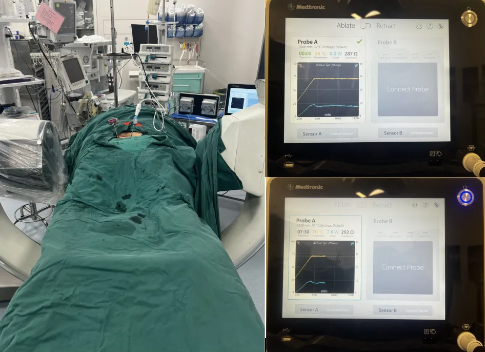

·患者朱某某,女,58岁,因反复腰背部疼痛半年,加重1周入院。腰背痛VAS评分7分。

·诊断:1.腰2椎体转移瘤(ESCC,2级);2.肺癌

智能控温射频消融能明显减少瘤体出血量(出血量50ml),为分离手术提供操作基础,降低输血依赖。分离手术实现充分减压,为后续放疗治疗提供可能性。